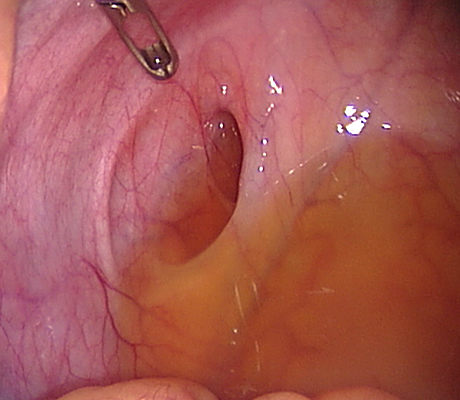

Diagnosis of endometriosis can only be done with certainty through a laparoscopy. Although this means surgery, a patient can also be treated at the same time, saving an extra procedure and the associated risks.

Laparoscopy is an operation (keyhole surgery) conducted under general anaesthesia. A telescope is introduced into a small incision in your navel, other small incisions are made for using special laparoscopic instruments and all the pelvic organs are examined with magnification (Video-laparoscopy) ; then the endometriosis is treated. Video Laparoscopy allows conservative surgery (hysterectomy is NOT the usual treatment for endometriosis) which means laparoscopic excision of the endometriotic implants, with restoration of the normal anatomy and preservation of the uterus, tubes and ovaries.